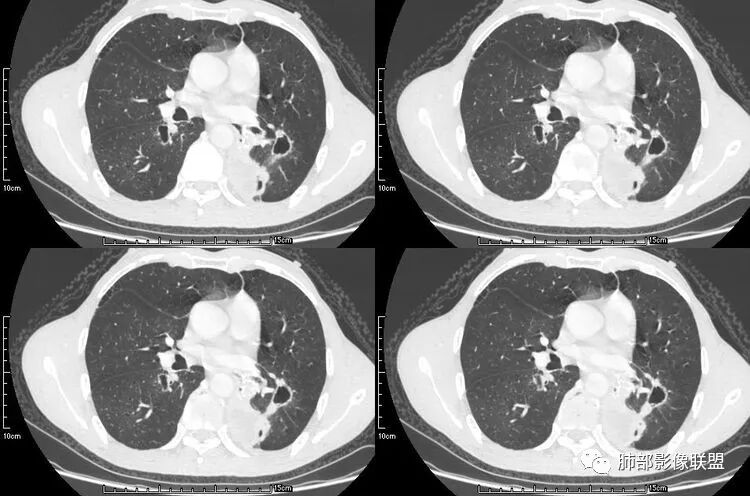

双肺多发结节,空洞,鬼脸,患者病程长,无发热,支持肺癌转移;

老年男性,咳嗽,咳痰带血2月,左下肺可见一团块影,深分叶,胸膜牵拉,可见坏死,坏死边界清,考虑恶性,双肺多发散在结节影,可见分叶,空洞,胸膜牵拉,考虑转移瘤;

双肺多发随机分布的结节伴空洞,部分囊内见空洞,分隔,壁结节呈假大空样改变,考虑肺腺癌伴转移或者全部为转移瘤。鉴别曲霉及血管炎,需要继续询问病史,有无免疫缺陷及鼻窦炎和肾功能的检查。

一开始看到多发空洞还有气囊,以为是金葡,但是病史不符合,部分空洞内有条索,左肺下叶病灶没有坏死,腺癌并肺内转移吧,鉴别曲霉,GPA;

张延军:双肺多发结节,空洞影,后者洞壁厚薄不均匀,部分腔内丝丝落落,呈分叶征,边缘见毛刺影,病灶大部分位于胸膜下,与血管相连,右肺下叶前基底段结节近段支气管截断,远端见空腔。左肺下叶病灶密度不均,背段支气管壁增厚,管腔狭窄。考虑1.双肺下叶占位性病变伴肺内空洞性转移 2.多原发的占位 3.肉芽肿性血管炎代排。

背景是慢阻肺背景。病灶是多发结节伴空洞,内部见结节影,即空洞内结节,符合得有:GPA,癌,结核,真菌(隐球菌,曲霉)

本病例左肺下叶肿块,有深分叶、毛刺、胸膜牵拉凹陷、支气管截断及纵隔内淋巴结肿大等征象,都均支持病灶为恶性,如腺癌,而且叶间裂的多发结节也提示是腺癌来源可能大;双肺多发结节、肿块,大部分病灶有分叶、毛刺及胸膜凹陷的恶性征象,与原发肿瘤本身的性质有关,所以应该与左肺下叶肿块同源,而且双肺多发病灶内空洞也具有多样性;

此病例中空洞形态多样,内壁不光整,有分隔影,周围未见明显卫星灶及钙化灶,结核不太符合;患者病史慢性病史,无明显发热,缺乏中毒临床表现,急性感染基本排除;各种中性粒细胞胞浆抗体阴性,没有鼻窦炎,肾脏等病史,基本排除血管炎;霉菌性空洞常见于免疫机能低下者, 常为空洞、肺炎、伴“ 晕圈”征的结节及支气管扩张合并存在。